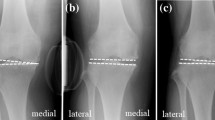

A total of 10 patients (consisting of 5 males and 5 females, or 5 right knees and 5 left knees, with the mean age of 53.5 ± 4.04 years) mainly with medial compartment mild KOA complicated with knee varus deformity were randomly selected from our hospital database from February 2017 to June 2017. Patients have to obtain informed consent and sign on informed consent documents before enrolling participants in this study. The mean body mass index (BMI) was 25.38 ± 2.24 kg/m2. The main clinical symptoms were medial knee joint pain. Imaging data revealed that the medial compartment of their knee joints was stenotic with mild damage in their cartilages. The X-ray revealed knee varus deformity with the mean varus angle of 7.17 ± 1.32° (Table 1). The patients had no pain relief from non-surgical treatments.

The model of the before PFO contains 53,256 nodes and 1,73,214 elements, and the model of after PFO has 49,359 nodes and 1,12,258 elements. The von Mises stress distribution in the knee reflected changes in stress pathways before and after PFO. Prior to PFO, both the tibia and fibula were loaded while the tibia was loaded much more than the fibula. Before the PFO, both the tibia and fibula were loaded while the tibia was loaded much more than the fibula. However, only the tibia was loaded after the surgery (Fig. 3). Stress distribution patterns of femoral cartilage, meniscuses, tibial cartilages, and tibial plateau before and after PFO were illustrated in finite element stress nephogram. It was found that the area of stress distribution in the medial femoral cartilage was larger than that in the lateral femoral cartilage. Stress in the femoral cartilage was reduced after PFO (Fig. 4). The area of stress distribution in the medial meniscus was larger than that in the lateral side preoperatively. After PFO, stress in the medial meniscus decreased (Fig. 5) but that in the lateral side increased (Fig. 6). Furthermore, stress in the medial tibial cartilage was reduced (Fig. 7) and that in the lateral tibial cartilage increased after the surgery (Fig. 8). The maximum stress loaded on the medial side of the cortical bone after PFO was lower than that before the surgery. Before the PFO, the stress on the medial side of the tibial plateau was greater. However, the medial stress on the tibial plateau decreased and the lateral stress increased after the PFO. The stress distribution in the cortical bone of the tibial plateau showed that stress was transferred from the medial area to the lateral area after the surgery (Fig. 9).

KOA with varus deformity is a common clinical disease with the main manifestations of pain in the medial compartment and knee joint function limitation. It brings about serious impacts on the daily life of elderly patients, and even can cripple some with severe KOA. Despite the favorable efficacy of TKA for the treatment of KOA with varus deformity [20], people have encountered problems, such as loose knee prostheses, prosthetic infections, dislocations, and bone resorption [21], in its clinical practices. So, researchers have refocused on safe and effective conservative treatments of knee arthritis and difficulties in their applications to avert these issues. A clinical study [22] has showed that PFO can improve both the radiographic appearance and knee function of patients with KOA. However, the mechanical evidences behind its efficacy remains insufficient. Some cadaveric experiments have uncovered that PFO can reduce stresses in the medial compartment of the knee. Yazdi et al. [23] have cut off the 20-mm long proximal fibulae in 6 cases and have found that the overall knee joint stress has been reduced, revealing a more significant decrease in the medial compartment stress with the maximum decrease of 21.6% and an increase in the lateral compartment stress with the maximum increase of 12.9%. In our finite element experiment, PFO changed the stress distribution in the knee joint and reduced the medial compartment stress especially in KOA patients. A clinical study concludes that the fibula supports one sixth of the body weight [13]. Therefore, PFO mainly helps rebalance or redistribute the load on the lateral and medial tibia plateau after surgery. In our finite element experiment, von Mises stress distribution in the knee before and after PFO illustrated variations of stress pathways in the knee. In particular, stress in the tibia significantly changed after the surgery. Another possible mechanism is the nonuniform settlement proposed by Yang et al. [10]. As people get older, they believe that the bone density of the knee tibial plateau reduces over time. For adapting to these changes, there may be no strong bone structural to support the medial side of the tibial plateau, but sufficient fibular support on the lateral side. Therefore, the rate of settlement inside and outside the tibial plateau becomes inconsistent. More medial-side settlements in the tibial plateau can result in knee varus deformity. Zhang et al. [13] have reported that the femoral condyle can medially shift during walking and sports with the presence of the transverse shear forces due to the tibial plateau slope arising from a nonuniform settlement. The support force on the lateral tibial plateau can be removed after PFO, which will relieve the medial compartment pressure and the resulting knee pain. Moreover, a three-dimensional gait analysis study demonstrated that PFO was beneficial for delaying the progression of knee arthritis [19]. This study provides with a significant quantitative approach for analyzing knee adduction moment in patients with KOA who present a 10–20% reduction in the overall peak knee adduction moment after PFO. In addition, a study of bone mechanics has reported that medial forces are reduced by 24%/30% on average during walking with the knee brace with mild (4°/8°) valgus adjustment [24]. Therefore, we speculate that the soft tissue of the knee joint can be rebalanced after PFO. Specifically, as the fibula tightly connects with the tibia prior to PFO, the lateral soft-tissue tension remains low. Once PFO has been performed, the head of the fibula will have greater freedom. After PFO, the soft tissue of the knee joint will form a new balance. The lateral ligaments and muscles of the knee joint will tighten while the medial side will relax. The lateral soft tissue of the knee will pull up the femoral condyle, reducing the tension of the medial tibial plateau. However, PFO also presents some limitations in correcting the alignment of the lower limb. A clinical study has reported that PFO is merely suitable for patients with mild varus deformity of the knee (≤ 5°) and has recommended applications of restorable spacers and four-point support plates to correcting alignment of lower limb in terms of severe varus deformity (≥ 5°) [25]. In our study, the average knee varus angle in KOA patients was 7.17 ± 1.32°, and post-PFO values of the maximal von Mises stress of femoral cartilage, medial meniscus, medial tibial cartilage, and tibial plateau in all patients were significantly lower than those before the surgery.